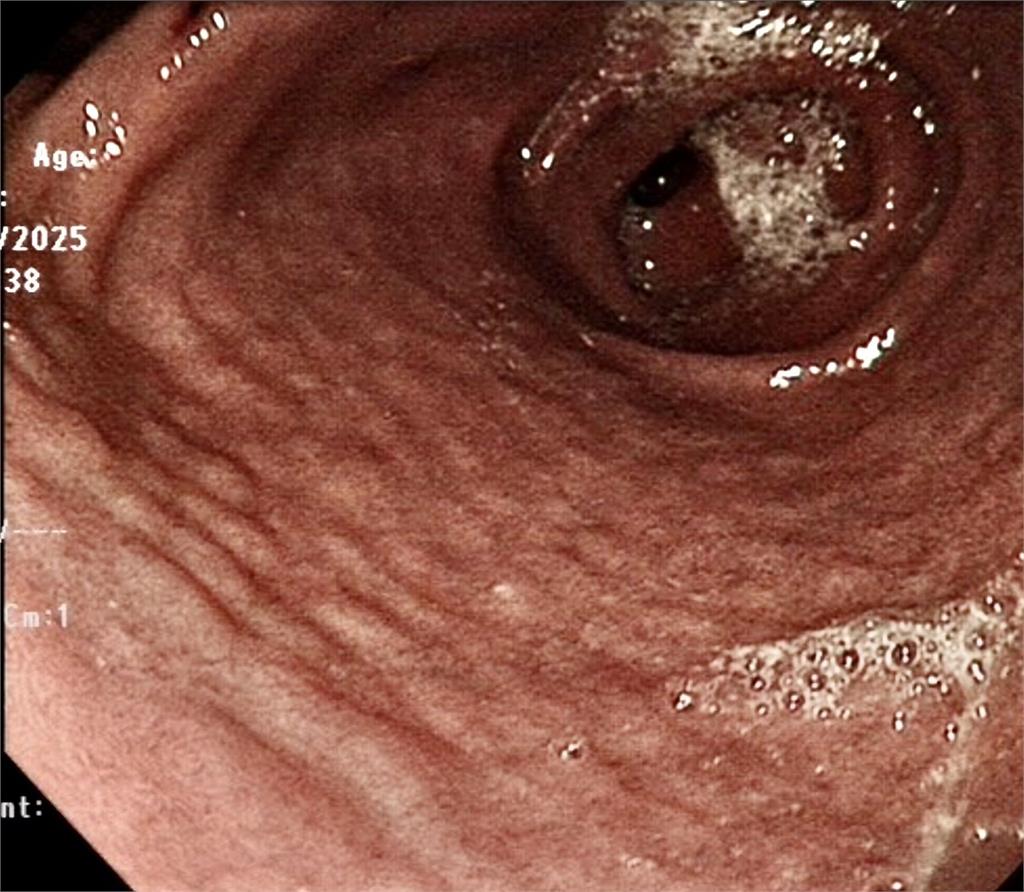

一名孩童近期因嚴重吐血緊急住院,沒想到在做胃鏡檢查時,醫師發現男孩的胃黏膜上布滿了一顆顆像是「鵝卵石」的突起物。切片證實感染幽門螺旋桿菌(H. pylori)。更令人揪心的是,病理報告顯示已出現「細胞異形增生」(low grade dysplasia),即所謂的癌前病變。